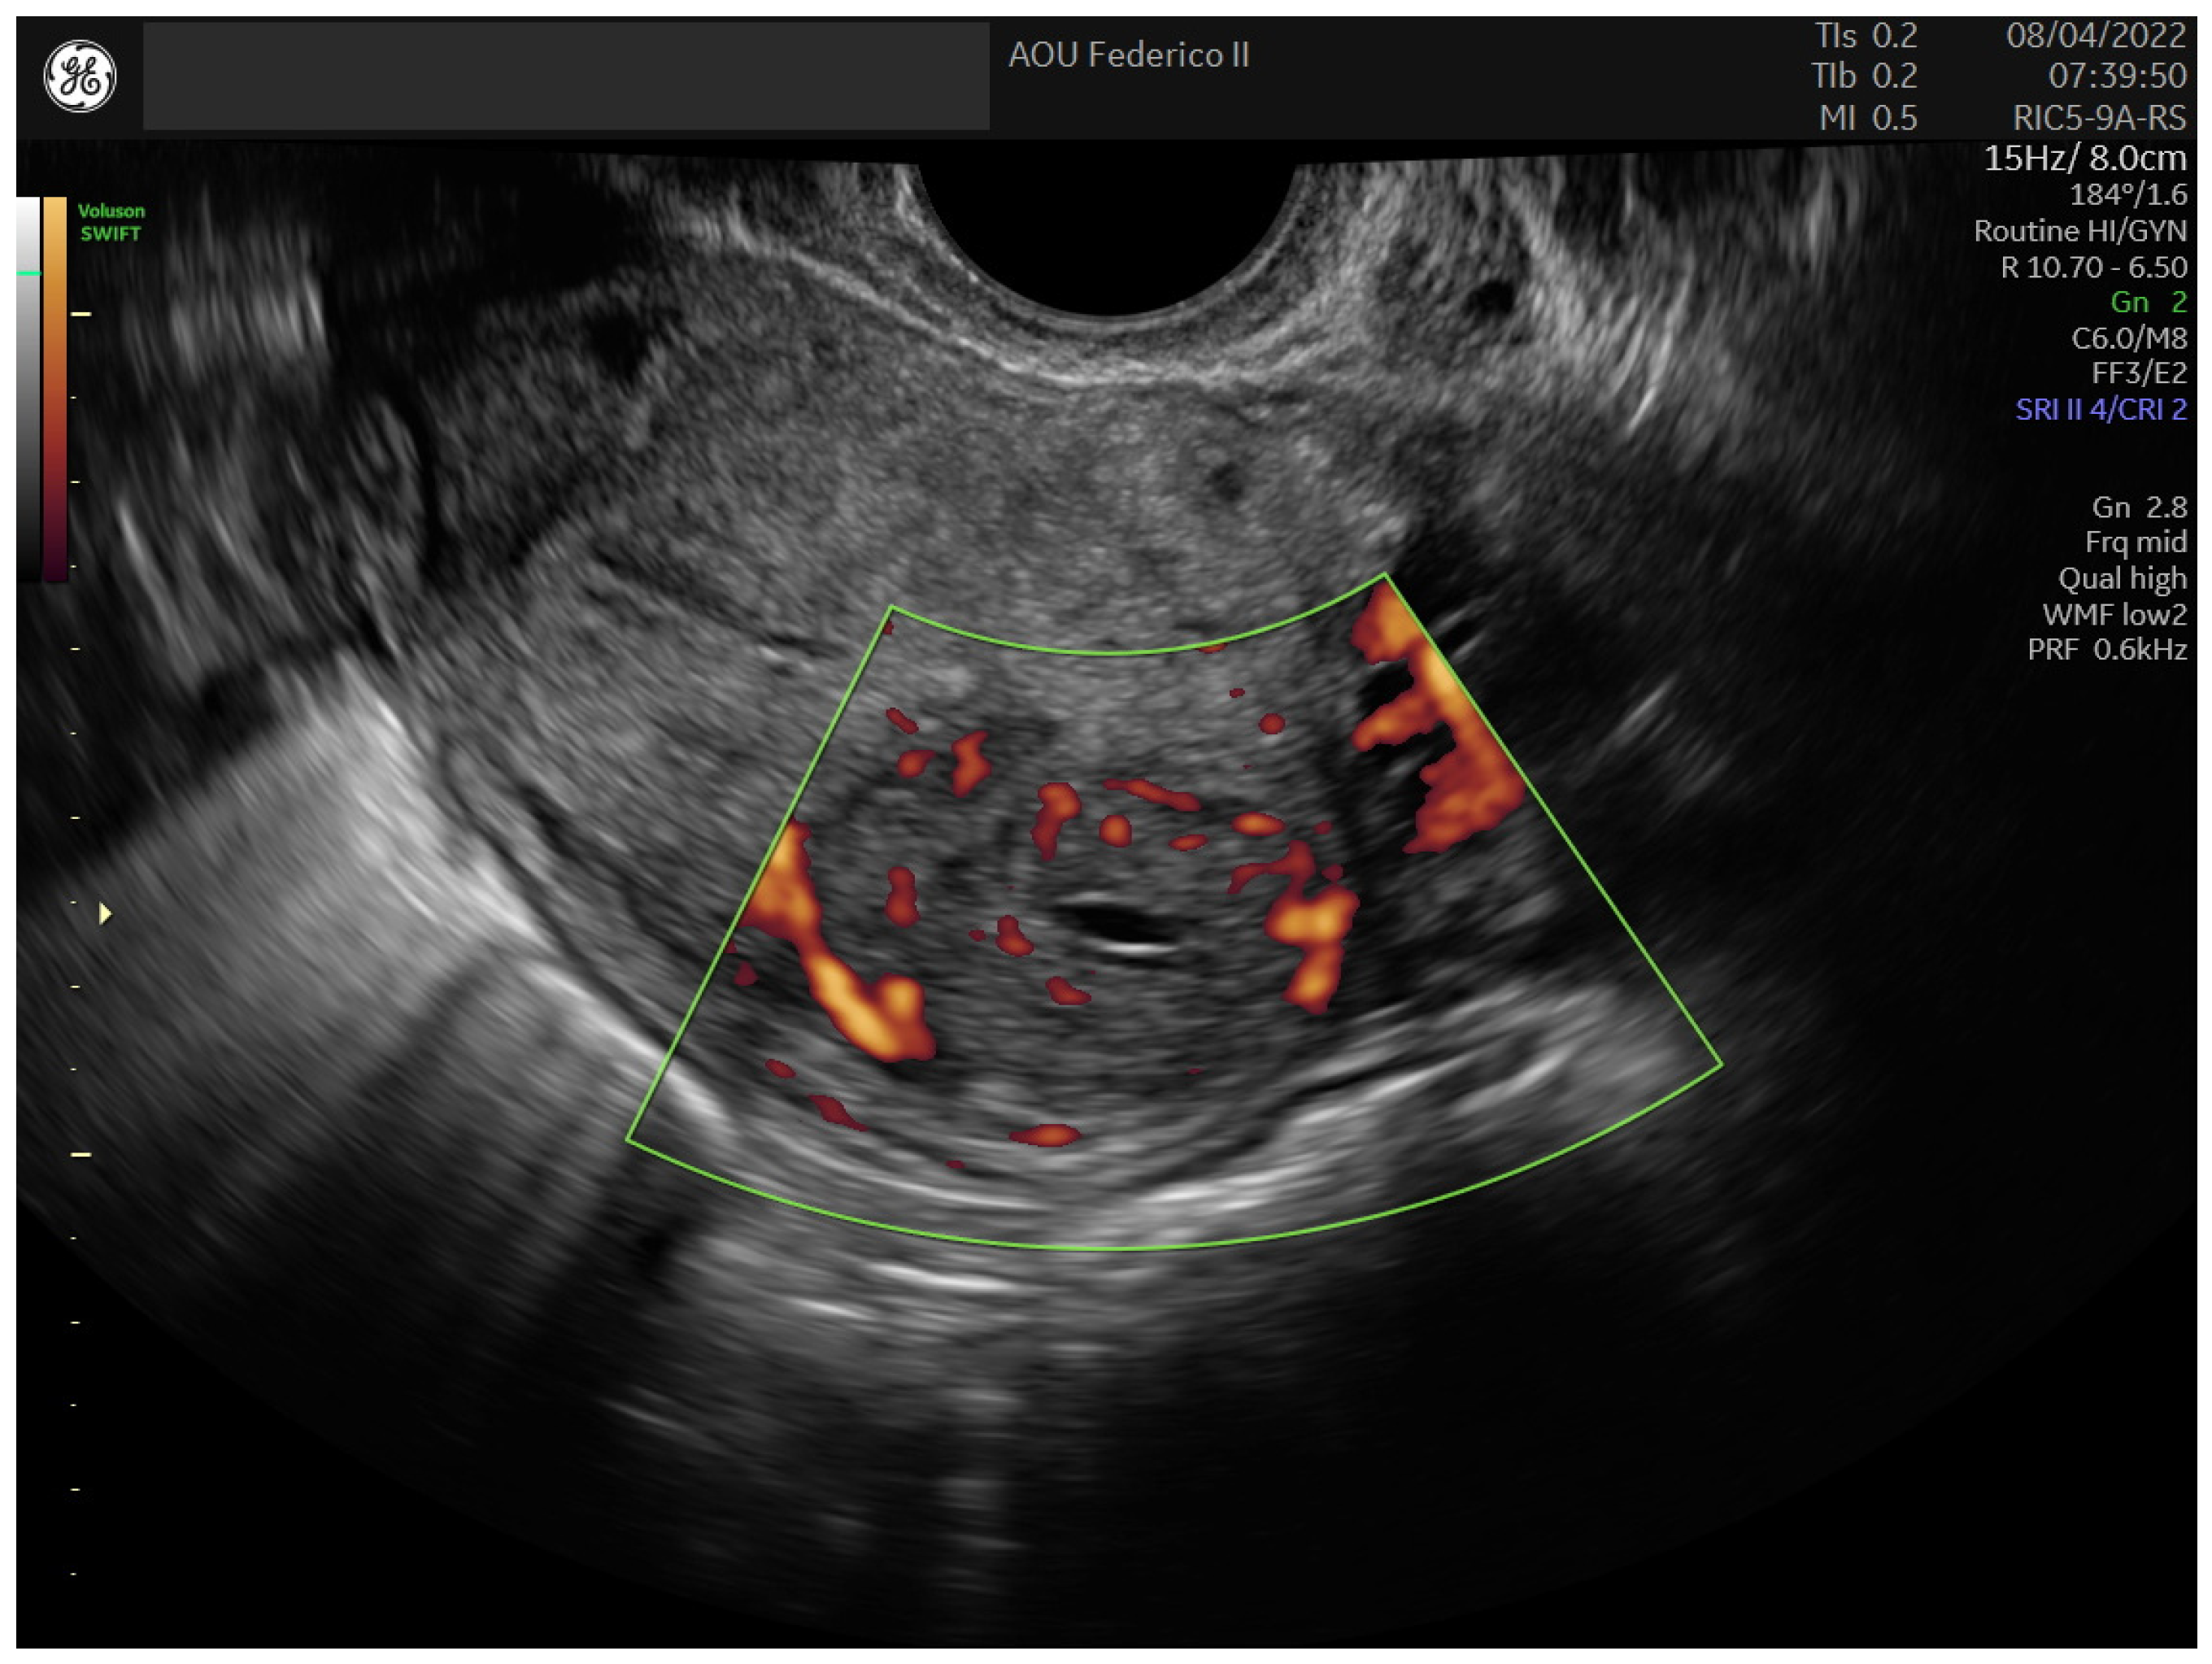

2.1. Case 1

2.2. Case 2